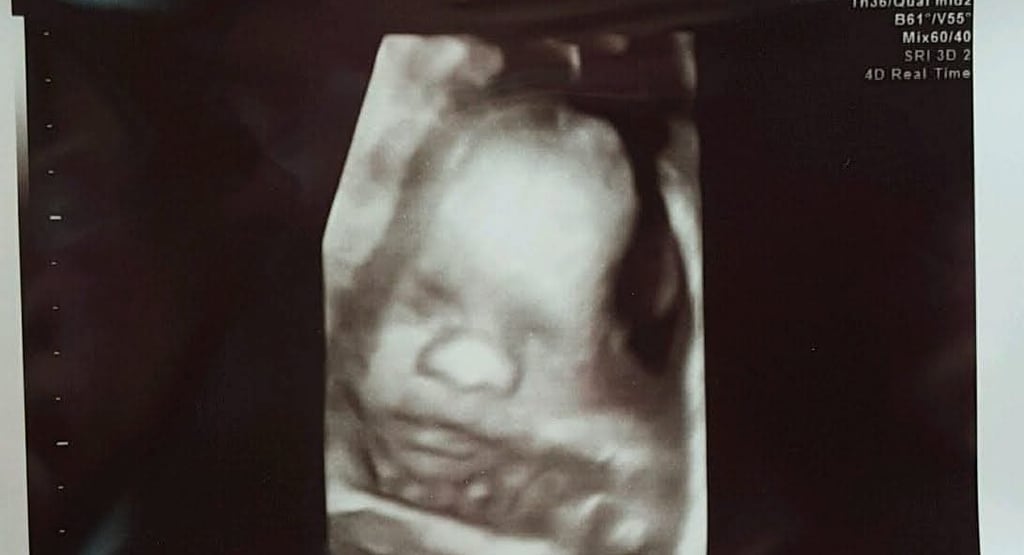

"There is no heartbeat." A statement that shattered my life almost 8 years ago. I heard this on a television show I was watching a few months ago and it stopped me in my tracks. Blindsided by that statement that kept me frozen on the couch for a few minutes.

"There is no heartbeat." One short sentence that brought so many emotions rushing back, taking me back to a time that was so painfully burned into my memory.

"There is no heartbeat." A statement that changed my life forever. For the first several months, I was crushed. It was isolating and I felt like a failure. BUT, that little heartbeat that once was gave me so much enlightenment. Avery's heartbeat was beautiful to hear as all my babies' heartbeats once did. The heartbeat during a pregnancy is a sound of joy, happiness and hope! Although my sweet Avery's heart stopped too soon, she had a purpose and made me a better person.